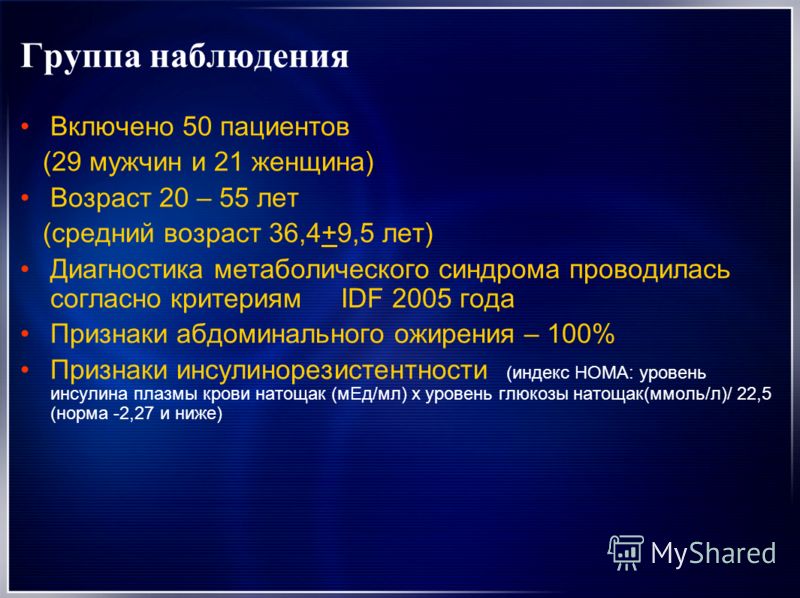

Роль легких в метаболических процессах

Раздел: Альбом идей